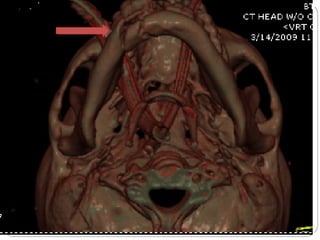

Computed Tomography (CT)

1. Also called CAT scanning or “CT”

2. X-Ray beam moves 360 around the patient

3. Consecutive x-ray “slices” around the patient

4. Computer can recreate 3D image of the body or

Image “slices” reconstructed by computation

5. Best for evaluating bone and soft tissue tumors,

fractures, intra-articular abnormalities, and

bone mineral analysis

Computed Tomography

6. The image formed is related to the subjects

density

7. Image display on computer or multiple films

8. New technology is multislice helical scanner